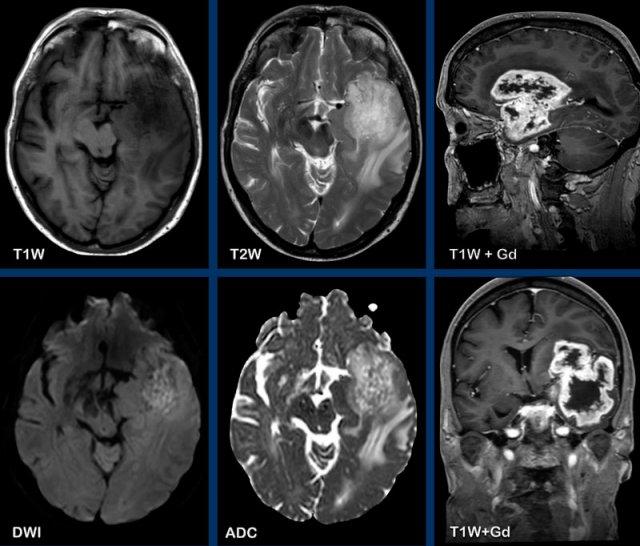

Các hình ảnh này của bệnh nhân 55 tuổi, nhập viện với các triệu chứng đau đầu và mất ngôn ngữ.

Hãy quan sát các hình ảnh trước rồi tiếp tục đọc.

- Các dấu hiệu hình ảnh là gì?

- Chẩn đoán có khả năng nhất là gì?

Hình ảnh

Ghi nhận một tổn thương vùng trán-thái dương trái, tăng tín hiệu trên chuỗi xung T2W, với vòng viền ngấm thuốc dày và không đều.

Tổn thương lan dọc theo và xâm lấn vào chất trắng theo hướng bó móc và các sợi chữ U.

Trung tâm tổn thương không có hạn chế khuếch tán và không ngấm thuốc, nhiều khả năng là vùng hoại tử.

Chẩn đoán có khả năng nhất là GBM (u nguyên bào thần kinh đệm).

Các u thần kinh đệm có nguồn gốc từ tế bào thần kinh đệm trong hệ thần kinh trung ương và là các u xâm lấn.

GBM là u não nguyên phát ác tính nhất.

Chúng xâm lấn lan tỏa dọc theo các bó chất trắng, ví dụ như thể chai.

Các hình ảnh này của bệnh nhân ung thư phổi di căn. Ghi nhận hai tổn thương di căn ngấm thuốc tại bán cầu não trái.

Trên chuỗi xung T1W có tiêm thuốc tương phản từ Gadolinium, các mạch máu cũng ngấm thuốc mạnh khiến việc phát hiện các tổn thương di căn trở nên khó khăn.

Trên chuỗi xung “black blood” (xóa tín hiệu máu), tín hiệu của máu trong lòng mạch bị triệt tiêu, giúp nhận diện các tổn thương di căn ngấm thuốc dễ dàng hơn.

Ở bệnh nhân này, điểm nổi bật là một tổn thương dạng nang lớn ở thùy đỉnh phải với vòng viền ngấm thuốc không đều và một phần dày.

Có hiệu ứng khối và phù não xung quanh, không có hạn chế khuếch tán.

Có thể nghĩ đến u thần kinh đệm.

Tuy nhiên, còn có nhiều tổn thương khác ở các vị trí xa nhau.

Một trong số đó có vị trí đặc trưng tại ranh giới chất xám – chất trắng (mũi tên).

Các tổn thương này được xác định là di căn não.